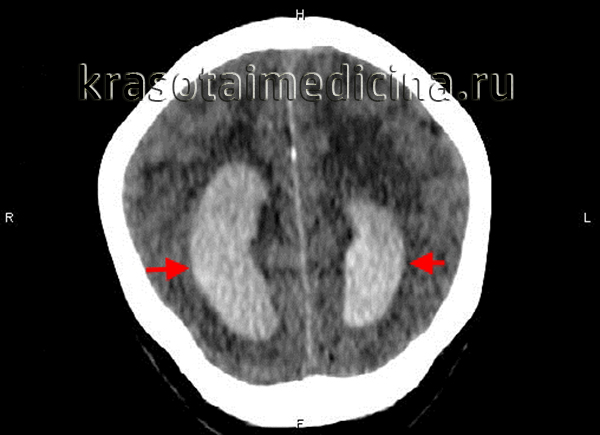

Кровоизлияние в желудочки головного мозга ( вентрикулярная геморрагия , внутрижелудочковое кровоизлияние )

Кровоизлияние в желудочки головного мозга – это патология, которая относится к ОНМК по геморрагическому типу. Синонимами данного заболевания являются вентрикулярная геморрагия (внутрижелудочковое кровоизлияние - ВЖК), геморрагический инсульт с прорывом крови в желудочки. Данная патология занимает первое место по смертности в мире.

Классификация кровоизлияний в желудочки мозга была разработана более 20 лет назад и внесена в международный классификатор болезней 10 пересмотра. Согласно МКБ-10, ВЖК подразделяют на несколько стадий: субэпендимальное кровоизлияние (СЭК), СЭК с распространением в боковые желудочки мозга, СЭК с распространением в желудочки и в вещество мозга. В клинической практике специалисты в области неврологии выделяют 3 вида внутрижелудочковых кровоизлияний: кровоизлияние в боковые желудочки, в III желудочек и в IV желудочек.

Кровоизлияние в боковой желудочек происходит из прилегающих к нему мозговых тканей и характеризуется постепенным заполнением объема боковых желудочков с распространением крови в III желудочек и далее. При большом количестве излившейся крови возникает значительное увеличение объема мозга с развитием двусторонней неврологической симптоматики. Если кровоизлияние сопровождается заполнением лишь одного бокового желудочка, оно имеет более благоприятное течение и симптоматику, напоминающую обычное паренхиматозное кровоизлияние.

При подозрении на кровоизлияние в желудочки головного мозга пациента нужно как можно скорее доставить в больницу. Не исключено, что в машине скорой помощи ему придется проводить реанимацию. В условиях стационара для подтверждения диагноза пациенту проводят: МРТ или КТ головного мозга, анализ крови с подсчетом количества тромбоцитов, исследуют коагулограмму, осуществляют мониторинг ЭКГ и АД.